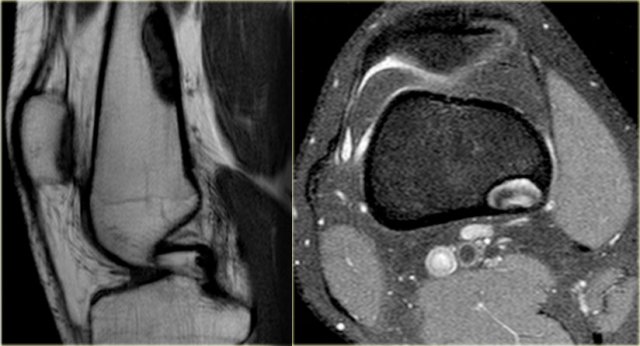

Study the images and then continue reading.

The findings are:

• Radiograph.

Homogeneous ossified mass adjacent to the cortical bone of the distal femur. Typical location and appearance of parosteal osteosarcoma.

• MRI

Sagittal T1-weighted MR image shows partial very low signal intensity due to the ossified matrix and the cortical bone which is unimpaired.